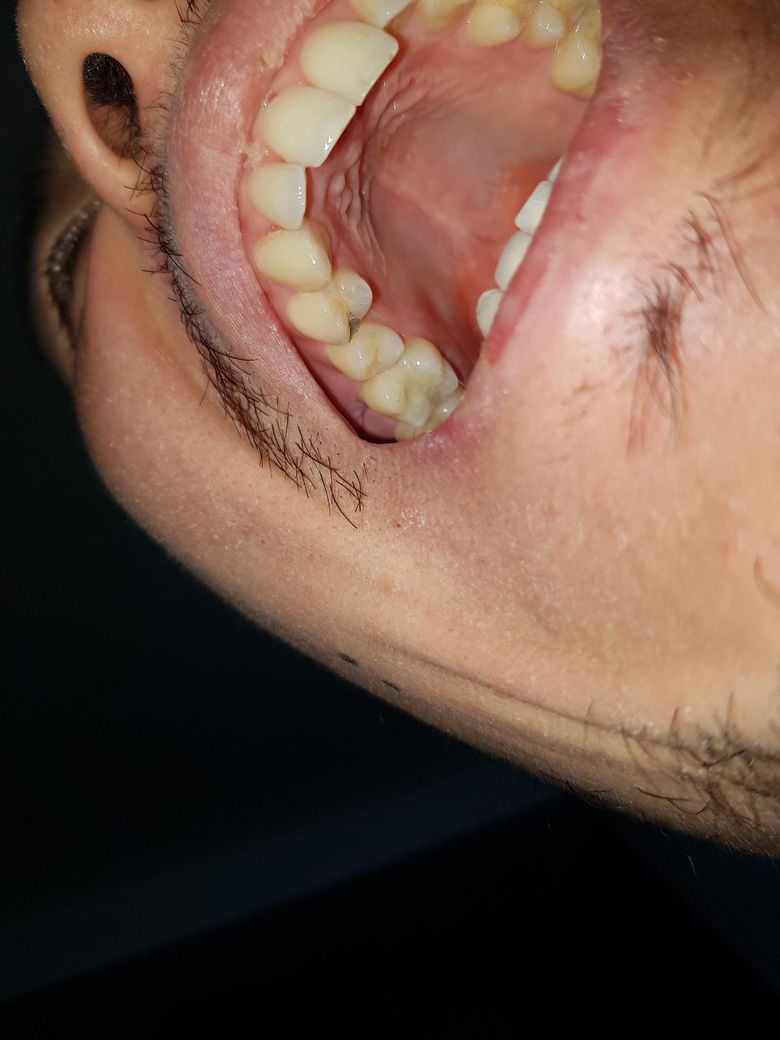

작년 12월말 씹었다 뗐을 때 아픈 증상이 있었고 그쪽으로 씹지말고 지켜보자하셨는데

2월초 잇몸이 갑자기 부었었습니다

항상 엑스레이후 이빨엔 문제가 없다고 하셨습니다 잇몸치료후 통증같은건 없었습니다

이때까지 달라진점은 음파칫솔을 사용하기 시작했고 이빨 잇몸사이 비스듬히 갖다댄다음 바로 지나가고 대고 지나가는식으로 했는데 이 진동이 원인이었을지 모르겠습니다

치실도 칫솔질전에 들어가서 왼쪽 오른쪽 슬슬하고 나오는정도로만 했습니다